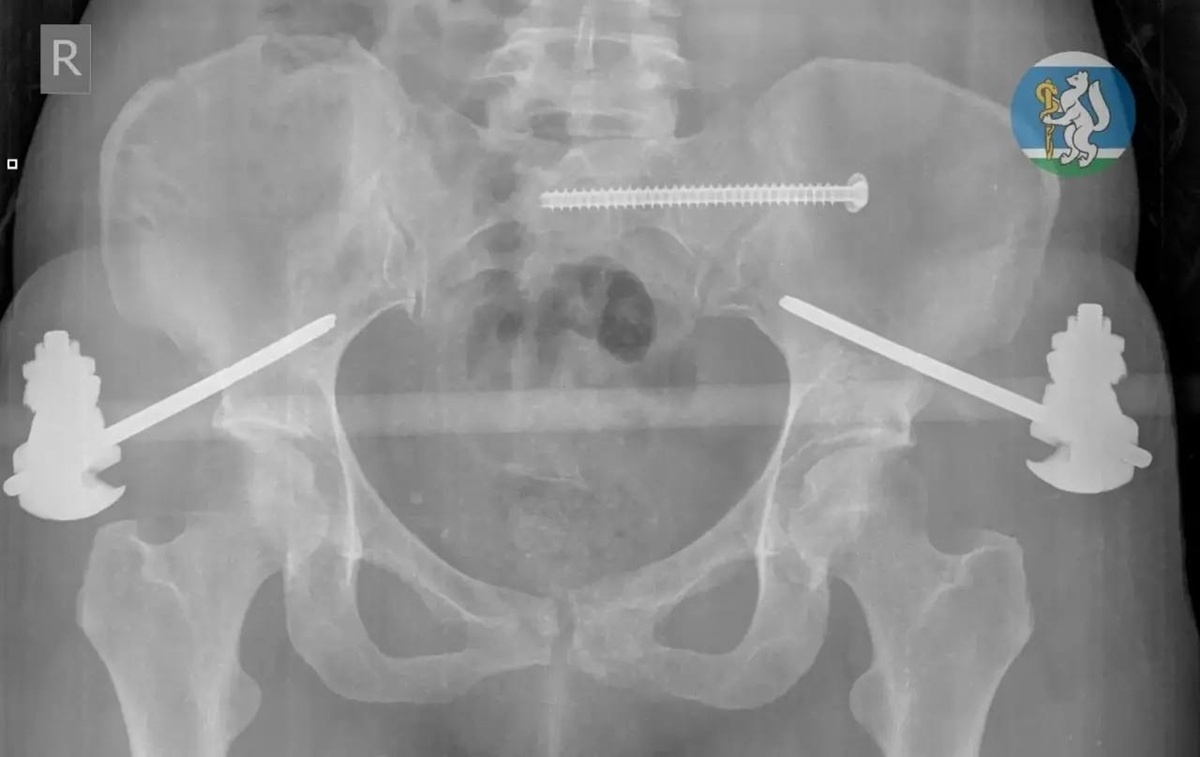

Врачи городской больницы №36 «Травматологическая» в Екатеринбурге спасли 36-летнюю екатеринбурженку, которая выпала из окна 7 этажа, когда мыла окна. В состоянии травматического шока женщину доставили на скорой в больницу. Медики ГБ №36 диагностировали у пострадавшей черепно-мозговую травму, множественные переломы костей таза, повреждение шейного отдела позвоночника, открытые оскольчатые переломы левой ноги, травму грудной клетки с повреждением лёгких. Большинство пострадавших с подобными травмами погибают ещё до приезда скорой. В больнице врачи вывели пациентку из шокового состояния, зафиксировали переломы, остановили кровотечение. Операция длилась несколько часов, женщина находилась на грани жизни и смерти. После экстренной операции пациентку перевели в реанимацию, где она до полной стабилизации состояния находилась на ИВЛ. В отделение травматологии её перевели через две недели, а ещё через две недели женщине провели операцию по частичному демонтажу аппаратов внешней фиксации и синте

Медики ГБ №36 диагностировали у пострадавшей черепно-мозговую травму, множественные переломы костей таза, повреждение шейного отдела позвоночника, открытые оскольчатые переломы левой ноги, травму грудной клетки с повреждением лёгких. Большинство пострадавших с подобными травмами погибают ещё до приезда скорой.

В больнице врачи вывели пациентку из шокового состояния, зафиксировали переломы, остановили кровотечение. Операция длилась несколько часов, женщина находилась на грани жизни и смерти. После экстренной операции пациентку перевели в реанимацию, где она до полной стабилизации состояния находилась на ИВЛ. В отделение травматологии её перевели через две недели, а ещё через две недели женщине провели операцию по частичному демонтажу аппаратов внешней фиксации и синтезу сломанных костей.